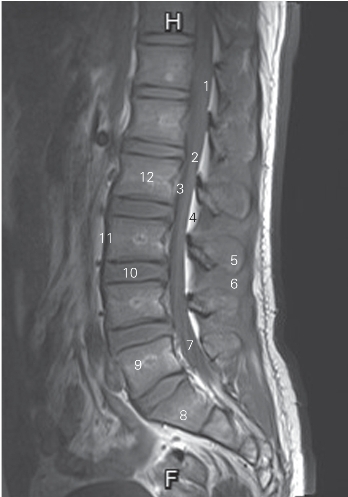

图3-11 经脊柱腰、骶尾段正中矢状断层MR T1加权图像

1 脊髓 spinal cord 2 脊髓圆锥 conus medullaris

3 后纵韧带 posterior longitudinal ligament

4 硬膜外脂肪 epidural fat 5 棘突 spinous process

6 棘间肌 interspinous muscle

7 终丝和马尾 filum terminal and cauda equina

8 第1骶椎1st sacral vertebrae 9 第5腰椎 5th lumbar vertebrae

10 第3腰椎间盘 3rd lumbar intervertebral disc

11 前纵韧带 anterior longitudinal ligament

12 第2腰椎椎体 2nd lumbar vertebral body